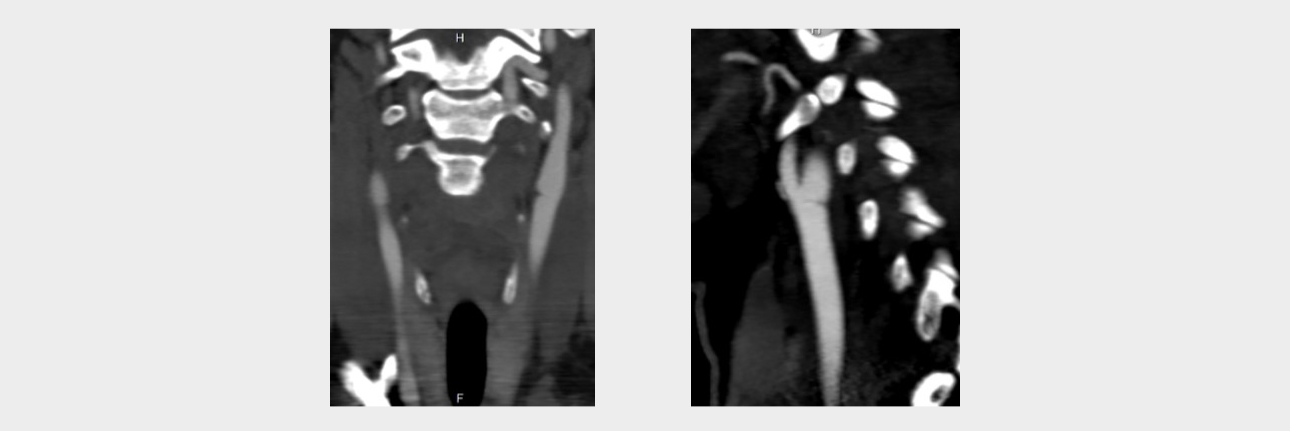

Computed tomography angiography

In order to clarify the changes detected on ultrasound, the patient underwent computed tomography (CT) angiography of extracranial arteries with intravenous contrast with Omnipack 350 in an amount of 50 ml on the SOMATOM Definition AS device (Siemens, Germany). According to the results of the study, linear structures were determined in the bifurcation of the common carotid artery on both sides, leading to a shelf-like defect in filling the vascular lumen in the sagittal scanning plane, more pronounced on the left (Fig. 5).

Conclusion: CT angiographic signs of the minimal variant of fibromuscular dysplasia (Carotid Web).

aotid-web-v-flow-fig5-pc

Fig 5. Computed tomographic angiography (sagittal scanning plane). Linear shadow (indicated by arrows) in the lumen of the bifurcation of the right (a) and left (b) common carotid arteries, leading to greater stenosis of the vessel on the left.

The results of the study confirmed the conclusion of ultrasound that the patient has a carotid network on both sides with a large stenosis on the left.